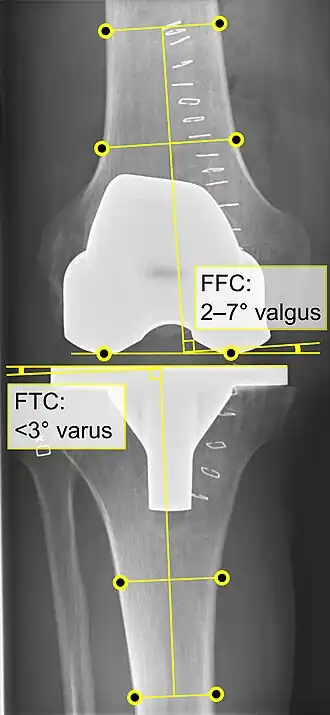

Knee replacement is routinely evaluated by X-ray, including the following measures:

- FFC: frontal femoral component angle. It is typically regarded as optimal when being 2–7° in valgus.[63]

- FTC: frontal tibial component angle, which is regarded as optimal when being at a right angle. A varus position of more than 3° has generally been found to increase the failure rate of the prosthesis.[63] -

- LTC: lateral (or sagittal) tibial component angle, which is ideally positioned so that the tibia is 0–7° flexed compared to at a right angle with the tibial plate.[63]